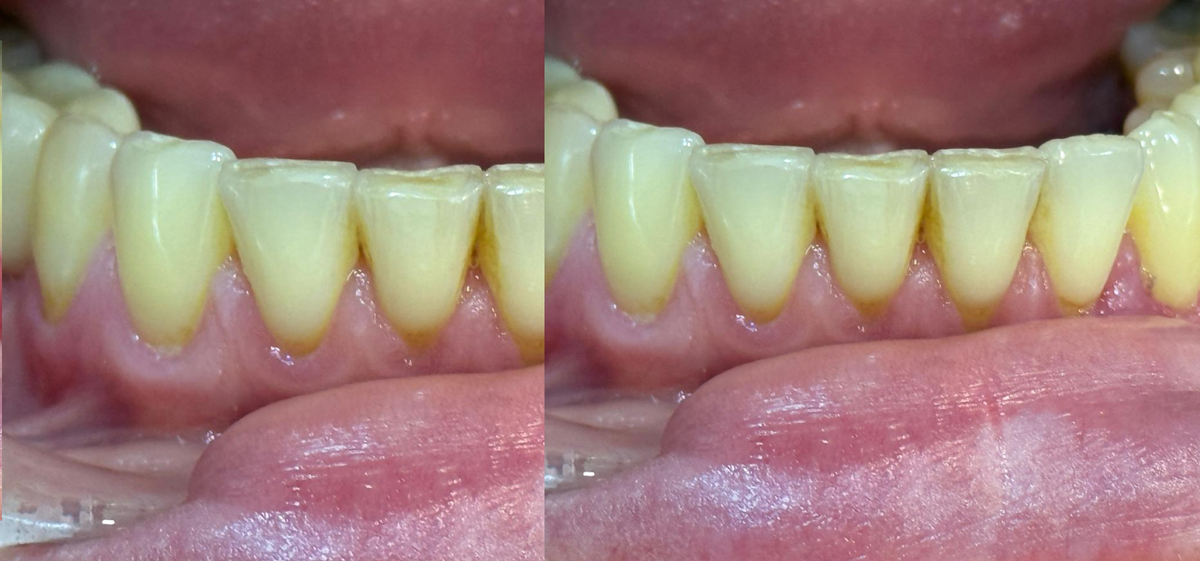

На фото видно три этапа: исходный дефект, сразу после коррекции и зажившая зона через 14 дней.

У пациента выраженная рецессия: корень полностью открыт, край десны неровный, зона чувствительная. Даже по фото видно, что ткани тонкие и уязвимые. В таком состоянии корень легко поражается кариесом и реагирует на холод.

Выполнили пластику рецессии с перемещением лоскута. Это не "подшивание ради красоты", а точечная реконструкция мягких тканей, чтобы вернуть корню защиту. Лоскут фиксирован тонкими швами - они стабилизируют новое положение ткани, а дальше уже включается физиология.

Что стало через 2 недели

И тут самое интересное. На фото видно, как корректно работает регенерация:

корень снова закрыт, линия десны стала ровнее, воспаление ушло, а чувствительность пациента почти полностью исчезла. Цвет мягко выравнивается, края становятся плотнее. Это только начало созревания тканей, дальше результат будет еще лучше.